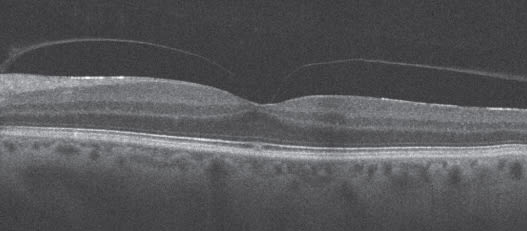

The more common conditions the cataract surgeon should be concerned about are vitreomacular traction syndrome and epiretinal membranes (ERMs), whether they are visually significant or not, because after cataract surgery, the vitreous may partially separate and cause more traction, and the ERM can become visually significant. That is not to say, however, that a premium IOL would be contraindicated in the presence of a minor epiretinal membrane because most are not visually significant, but certainly it should be documented preoperatively. These membranes can be quite subtle, but with Cirrus SD-OCT B-scan (Figure 1) and C-scan, diagnosis is simple. The cataract surgeon may decide to send the scan to the retina specialist to determine whether or not the ERM is visually significant, and to discuss which type of IOL should be implanted, and if the macular problem should be addressed before or after the cataract surgery.

Figure 1. Determining if an epiretinal membrane is present before cataract surgery is an important step in patient management and can be done easily with Cirrus HD-OCT.